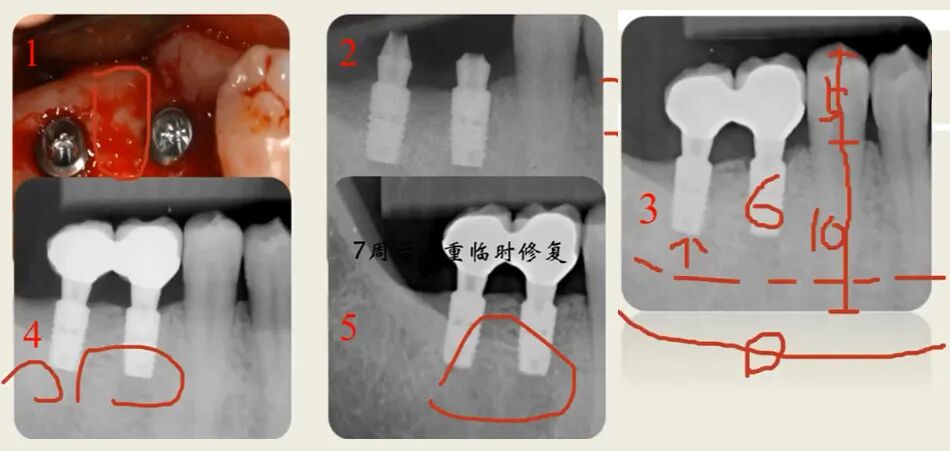

曲面断层片怎么看种植术前读片,学会看CBCT、曲断片、根尖片_https://www.jmylbn.com_新闻资讯_第3张

曲面断层片能不能用来种牙?

曲面断层片可看全貌但看不了横断面,例如前牙唇腭侧断面、后牙骨板厚度、后牙颊舌向断面,可能会造成备洞侧穿的后果,但可通过术前术后对比发现,还可以用骨形貌图弥补曲断的不足,通过描出关键结构测算骨高度。